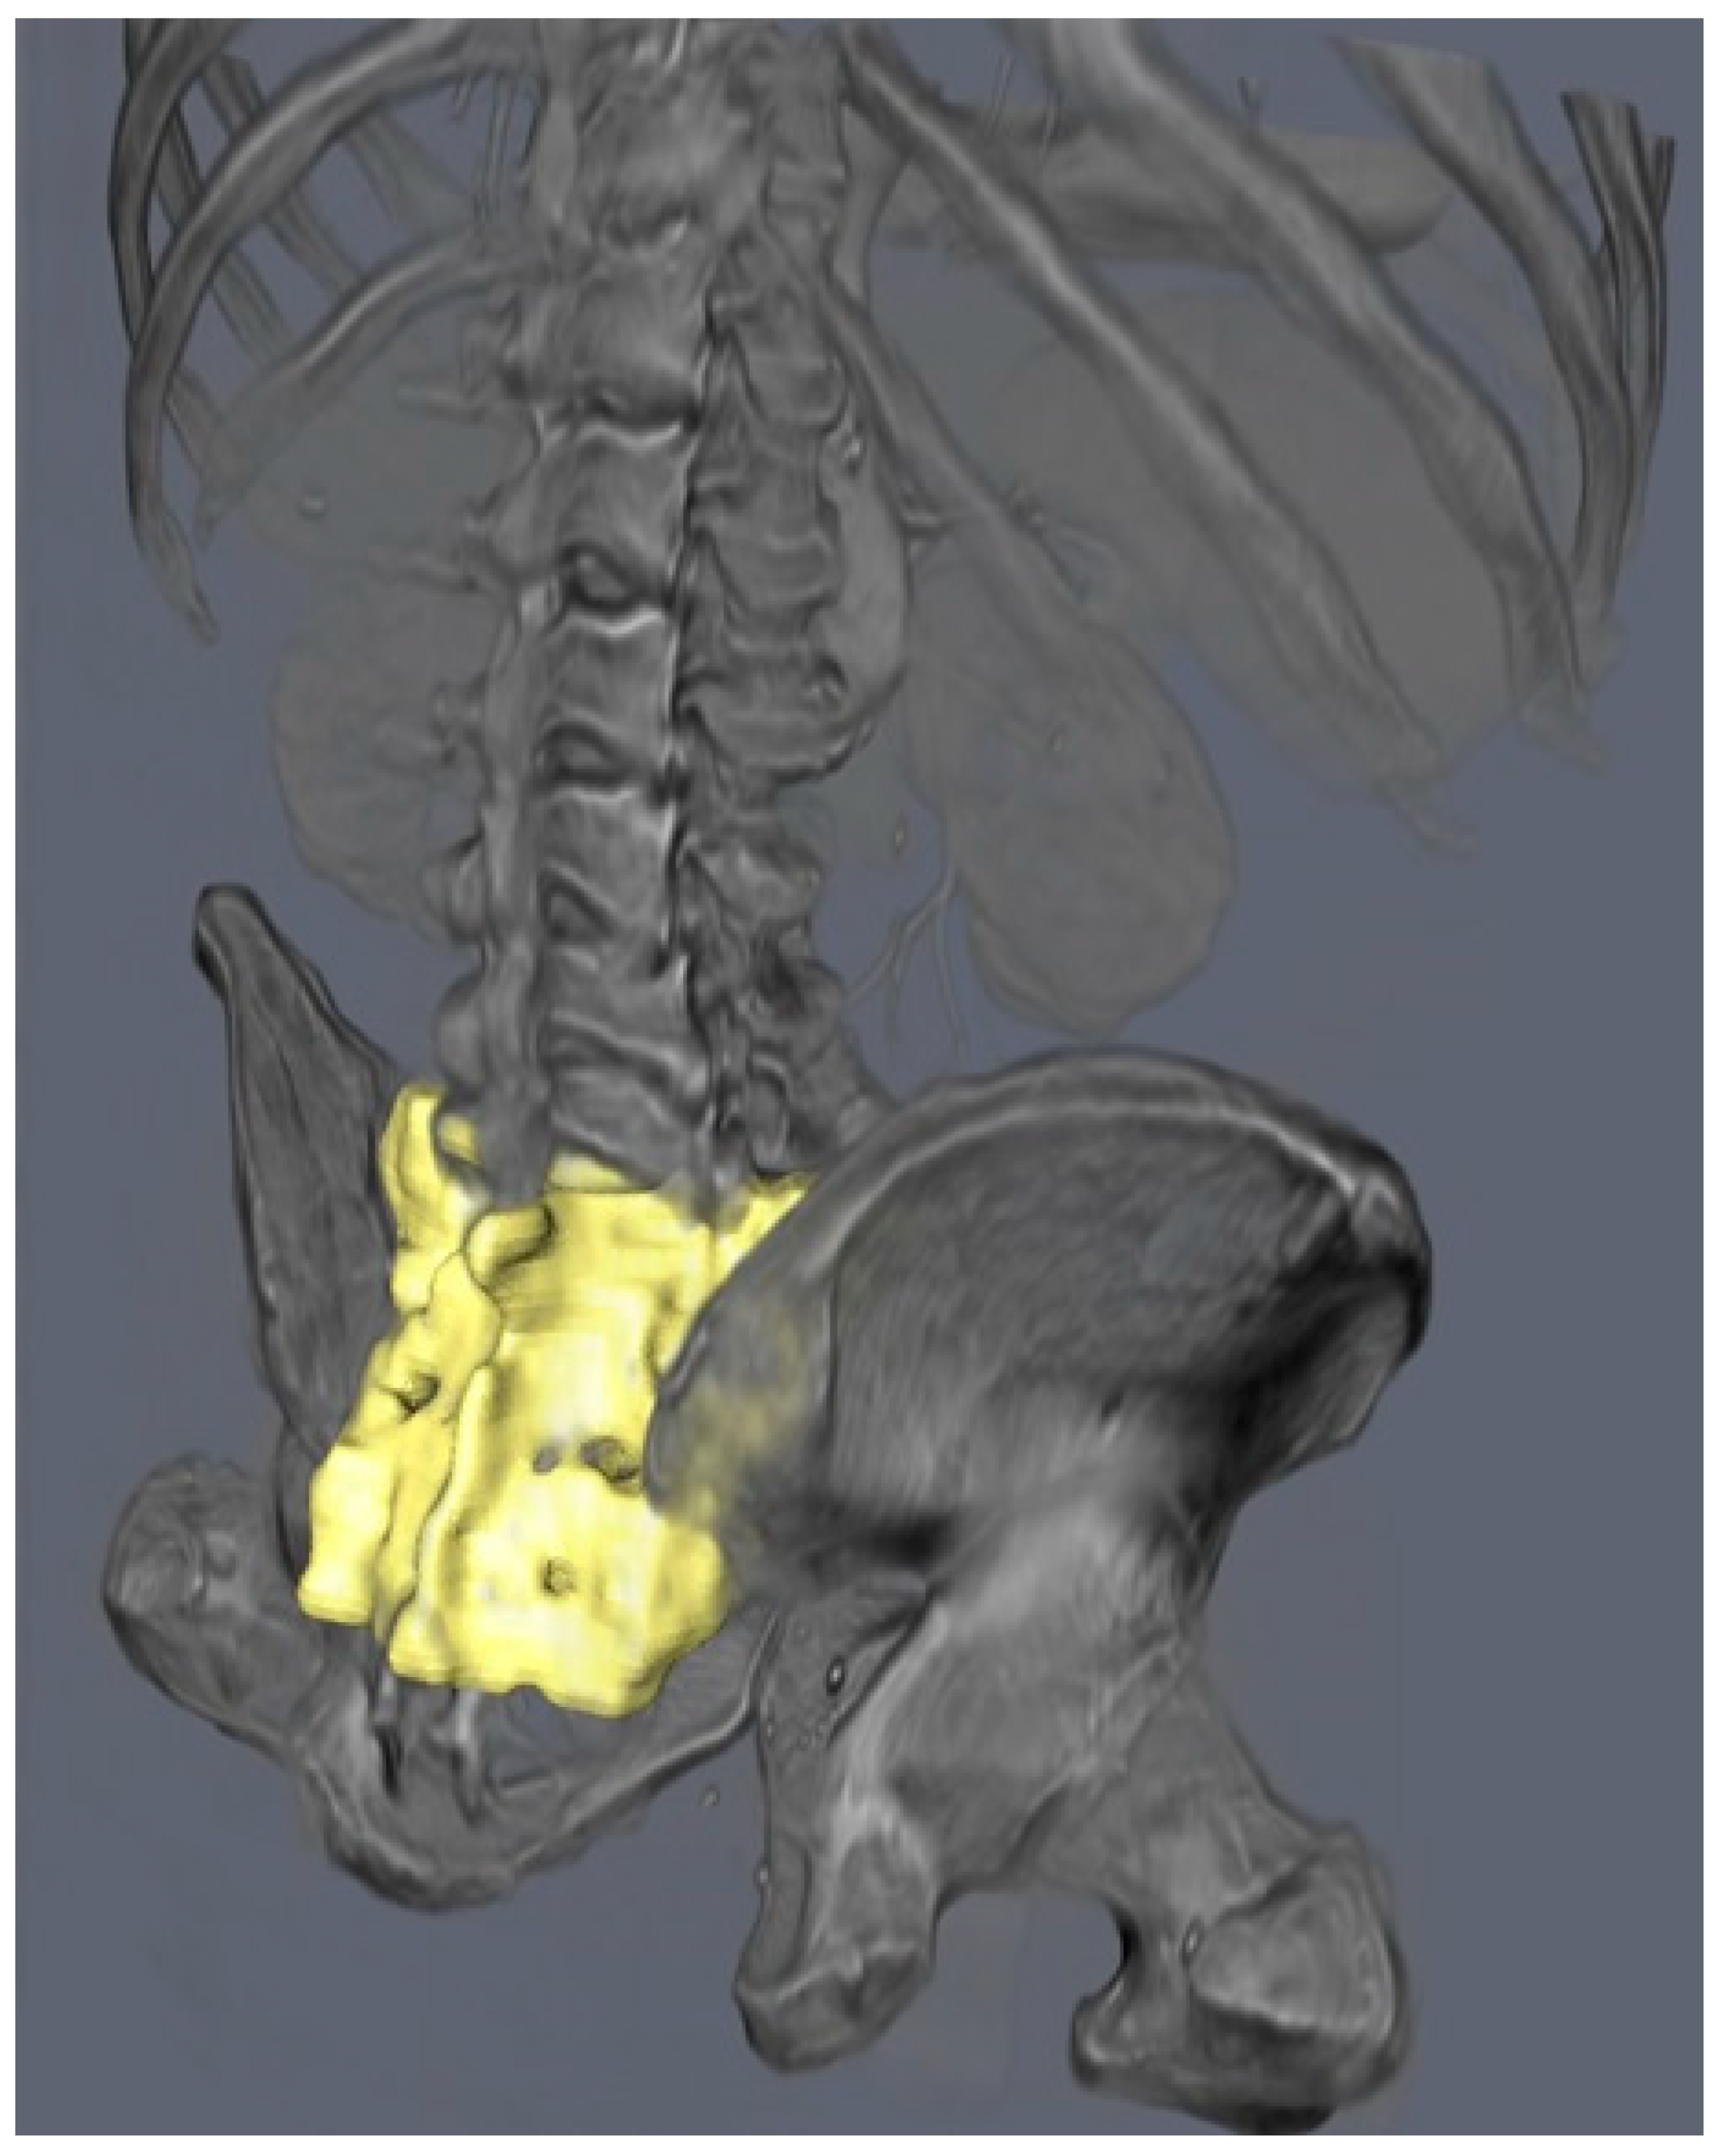

- Manual Segmentation: Initial segmentation of the SI region was performed manually using Avizo software (version 2020.3, Thermo Fisher Scientific, Waltham, MA, USA). Standard thresholding techniques were attempted; however, due to the relatively low bone density in the SI region, these methods were ineffective in accurately delineating the joint.

- Freehand Segmentation: To overcome the limitations posed by the low-density bone structure, a freehand segmentation approach was employed. This method, which involved manually tracing the boundaries of the SI region, took approximately one hour to complete. The result was a high-precision binary mask of the SI region, which was then used to create an accurate 3D model of the joint.

3.1. Three-Dimensional Model Creation and Segmentation